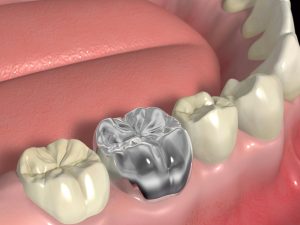

Один из самых популярных и доступных методов восстановления целостности зубов при запущенном глубоком кариесе и пульпите – установка зубных коронок. Цельнолитые металлические коронки были востребованы 2-3 десятилетия назад. Их изготавливали из золотого, стального и серебряно-палладиевого сплава. С приходом в стоматологию керамики спрос на металлические коронки резко упал, но из-за ряда преимуществ их устанавливают и сейчас.

Виды цельнолитых коронок

Специфика цельнолитых металлических коронок заключается в методе изготовления. Изделия выполняются в зуботехнических лабораториях по технологии литья. В отличие от устаревших штампованных пластмассовых коронок, цельнолитые отличаются точным прилеганием к зубу, отсутствием избыточного давления на десневые ткани, прочностью и высокой функциональностью. Биосовместимые материалы коронок предотвращают раздражения и воспаления в пародонте.

Цельнолитые коронки выполняются с напылением и без. В первую категорию входят и протезы с керамической облицовкой.

Очевидным плюсом цельнолитых металлических коронок является высокая прочность. Гипоаллергенные сплавы защищают от аллергических реакций, воспалений в мягких тканях, раздражений десен и отторжения инородных тел. Изготовление протезов путем литья делает прилегание к опоре максимально органичным и естественным.

К минусам относят неестественный внешний вид металлической коронки. Для повышения эстетики проводят керамическую облицовку изделия, но это увеличивает итоговую стоимость конструкции.